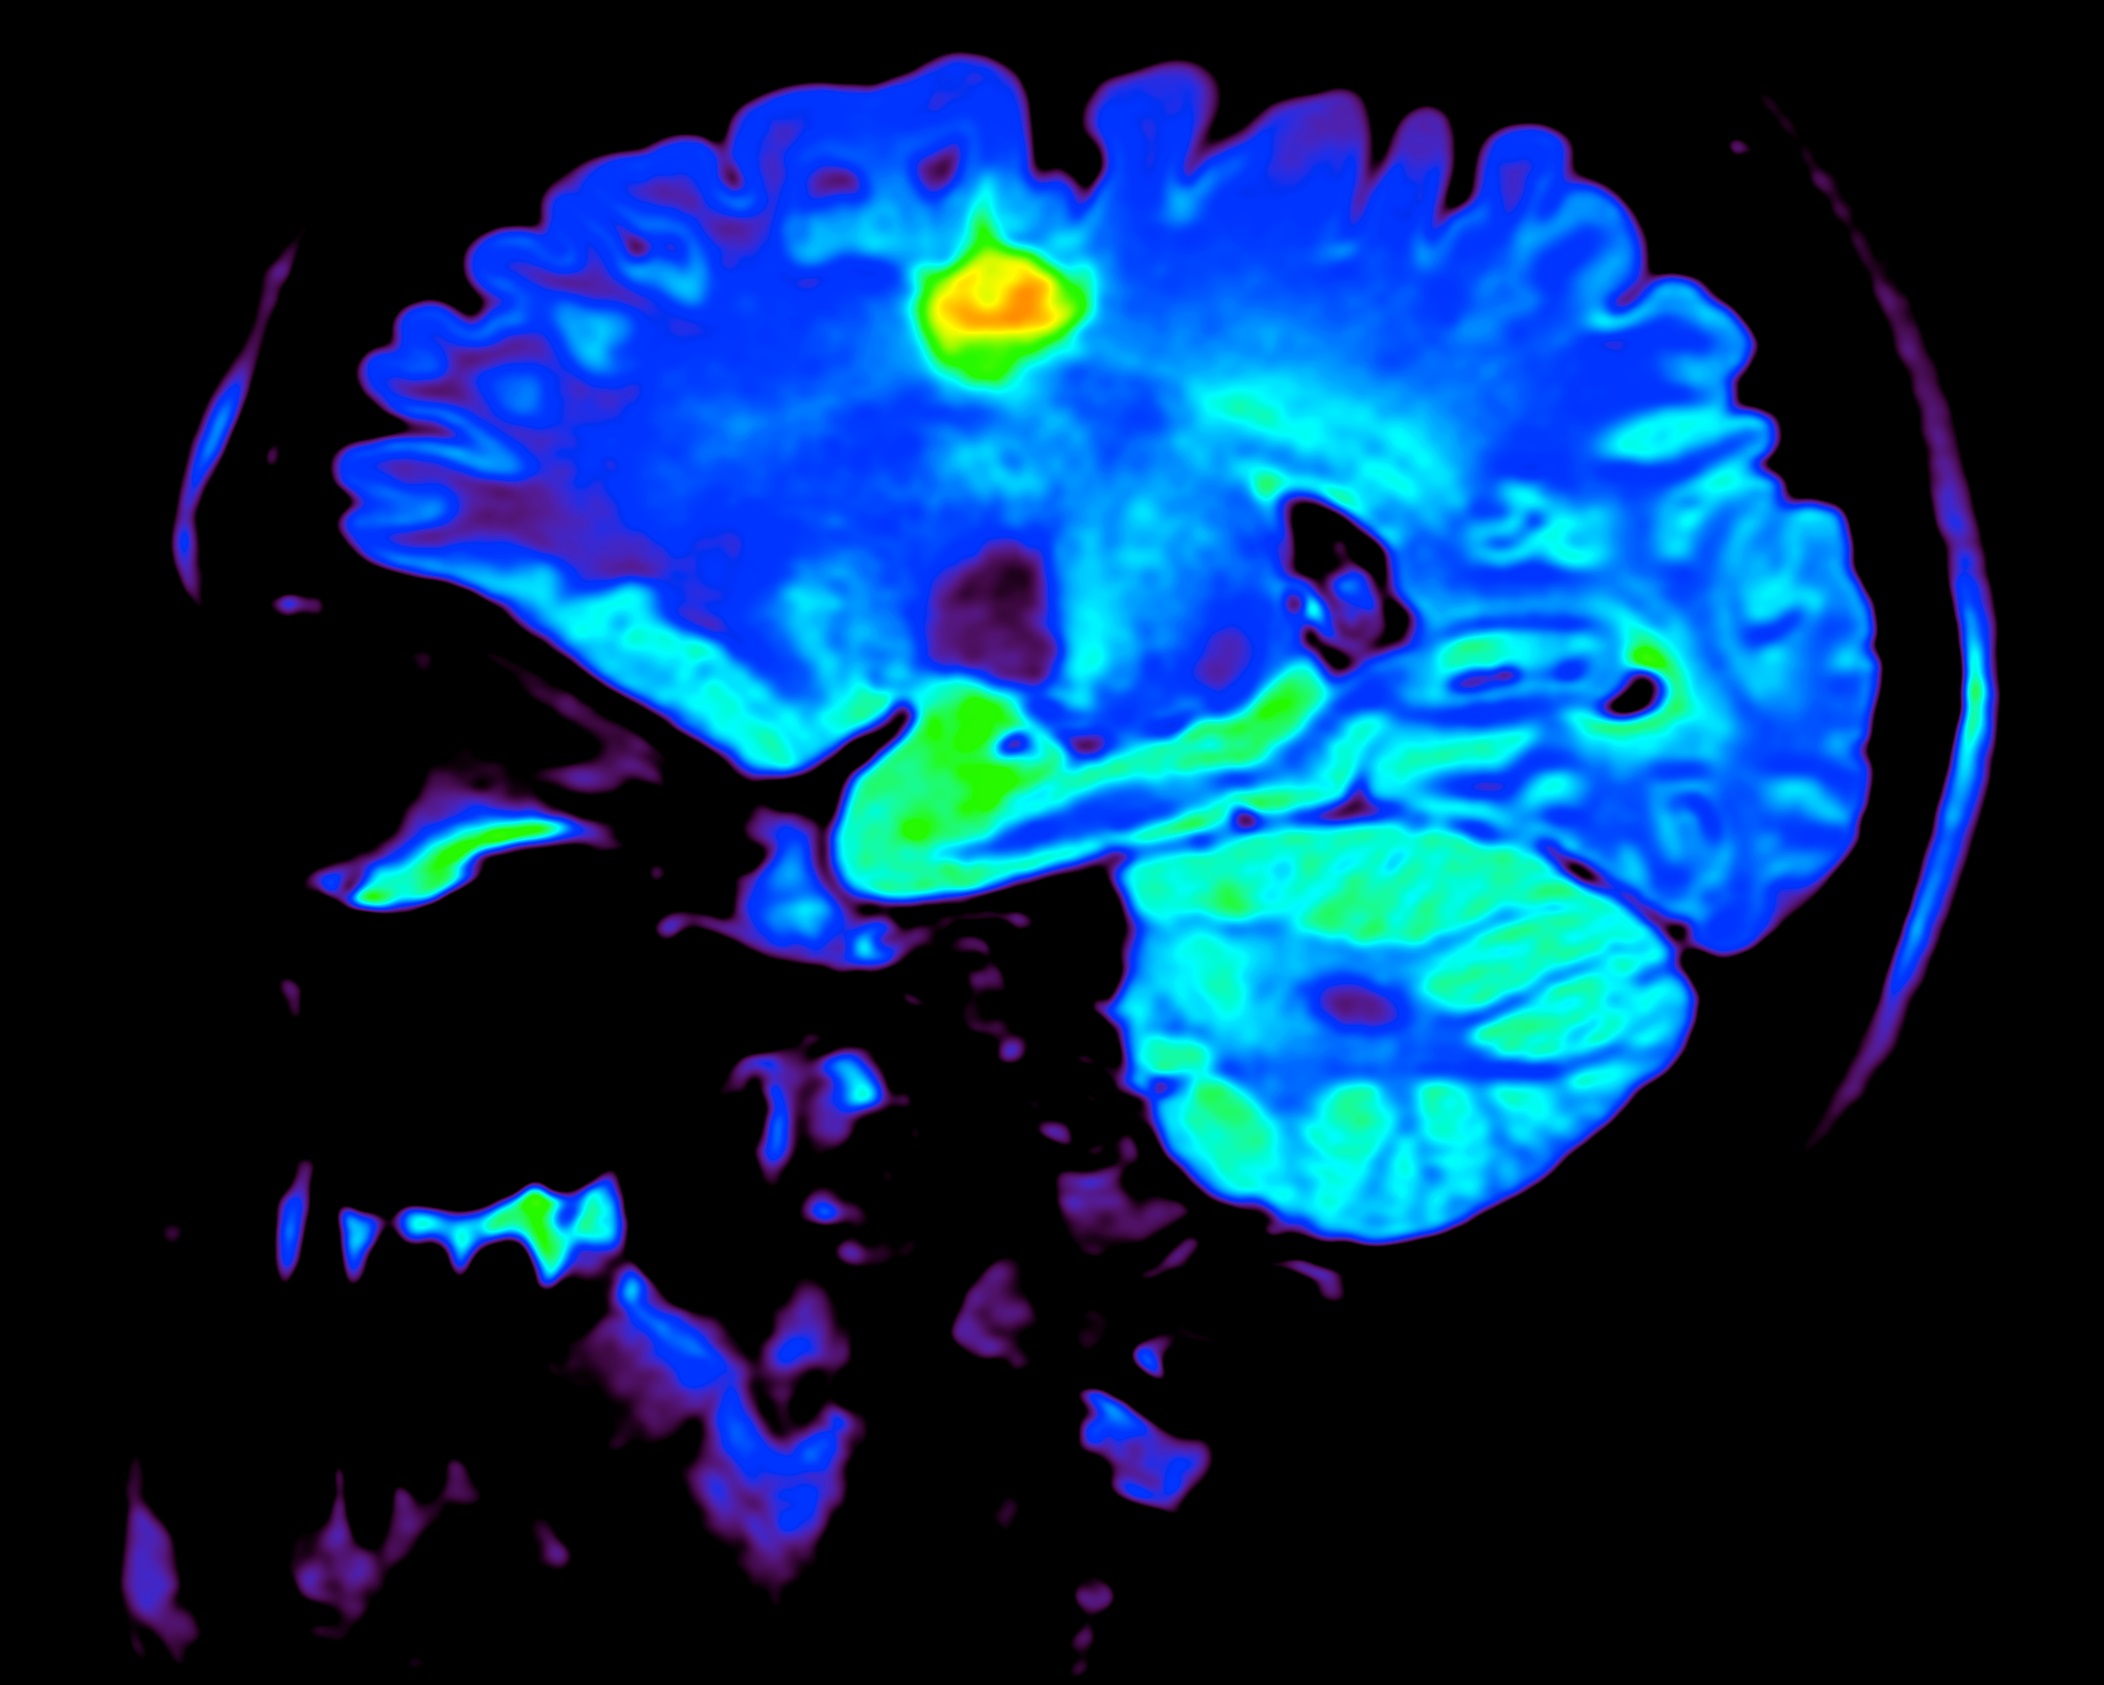

Okuda’s team analyzed MRI scans of MS-affected brains and printed exact copies of the lesions, or damaged areas, detected in them. These were given to people who would normally have just used 2D images or a 3D reconstruction on a screen to diagnose or monitor this type of thing.

“What you see on plain 2-dimensional views does not give one a clear understanding as to the true shape of the lesion itself,” Okuda told me. “By studying lesions in 3D, we are looking at these findings in an entirely different way, assessing their shape and surface characteristics.”

They identified a number of features that distinguish MS lesions from other types of brain damage, such as asymmetry and complex surface structures. These weren’t always obvious from scans and the transition to 3D let the participants more easily perceive them.

“Prior to the release of our work, we were describing multiple sclerosis lesions incorrectly,” said Okuda. “Lesions from MS are still described as being ‘ovoid’ in shape and ‘well circumscribed’ in character. Based on our 3D work, we know that this is not the case. We were amazed at the complexity of MS lesions and would argue that conventional terms previously used in our field may not be accurate after a review in physical 3D form.”